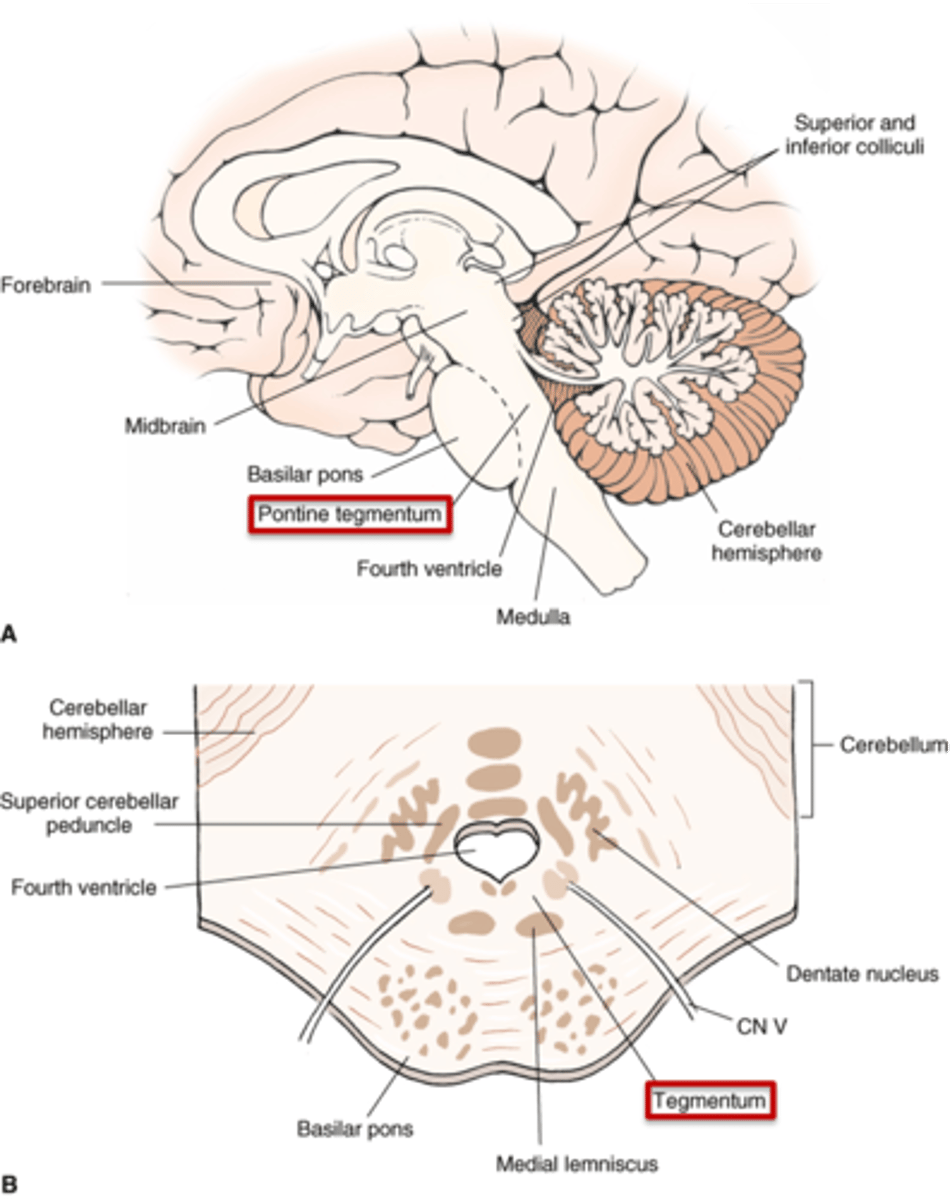

what are the 4 areas that the brainstem can be divided into (from posterior to anterior)?

1. tectum

2. ventricular system

3. tegmentum

4. basal portion

which area of the brainstem is the roof over the ventricular system?

tectum

which area of the brainstem makes up the core of the brainstem?

tegmentum

which area of the brainstem is situated most anteriorly?

basal portion

what are the 2 components that make up the ventral and dorsal area of the pons?

1. basilar pons (ventral)

2. tegmentum (dorsal)

what component of the pons forms the floor of the fourth ventricle?

tegmentum